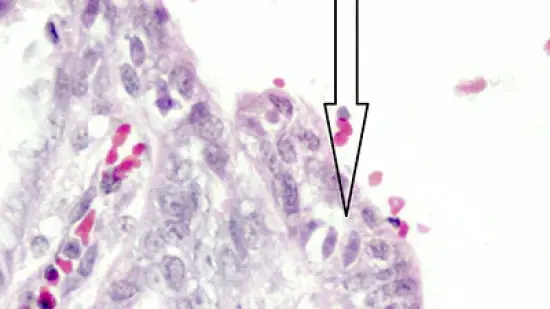

Quale microrganismo (freccia) si trova all'interno della mucosa dell'intestino tenue di questo suinetto con diarrea?